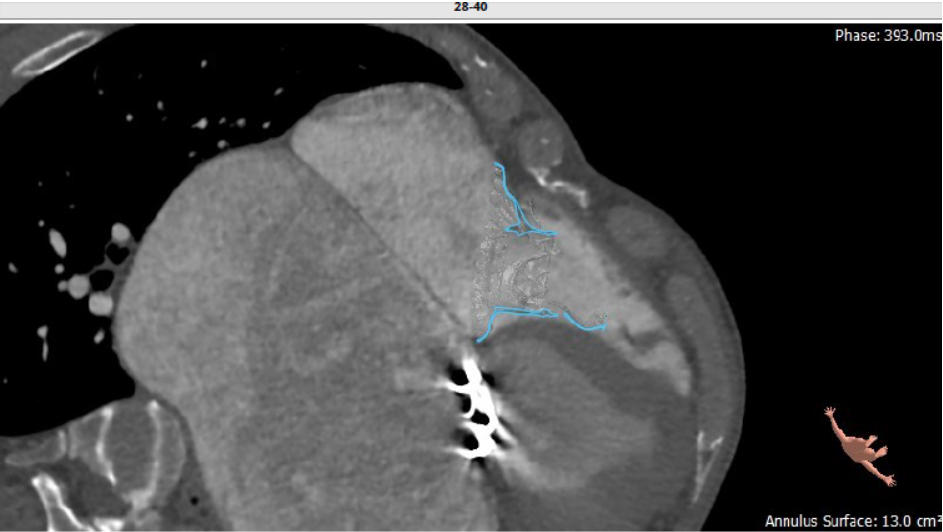

长海医院心外科徐志云、陆方林团队综合该患者CT、超声检查结果,对该患者的情况进行了充分的评估和讨论,决定采用LuX-Valve®瓣膜系统对患者进行微创治疗。手术于7月12日上午在长海医院导管室进行。根据术前CT的测量结果,选择使用JS/TTVI-30-55型号的LuX-Valve®瓣膜。只需在患者右侧第五肋间开一个小孔,经右心房穿刺,在心脏不停跳的情况下,用导管将介入瓣送入右心室,反复调整瓣膜位置,最终超声确认无瓣周漏后对瓣膜进行锚定。术后超声和造影显示瓣膜位置良好,无明显反流。

第二例患者为56岁男性,25年前接受了“主动脉瓣+二尖瓣机械瓣置换术”,约18年前出现三尖瓣关闭不全,近年来复查彩超示三尖瓣反流逐渐加重伴轻微黄疸、双下肢水肿,虽长期服用利尿剂治疗,但效果越来越差。长海医院心外科徐志云、陆方林团队综合该患者CT、超声检查结果,对该患者的情况进行了充分的评估和讨论,决定采用LuX-Valve®瓣膜系统对患者进行微创治疗。手术于7月12日下午进行,由于病人左心房扩大压迫右心房,心室游离壁距离瓣环中心仅29.8mm,再加上室间隔与瓣环夹角过大,手术操作有一定难度,瓣膜锚定也需要相当的经验。